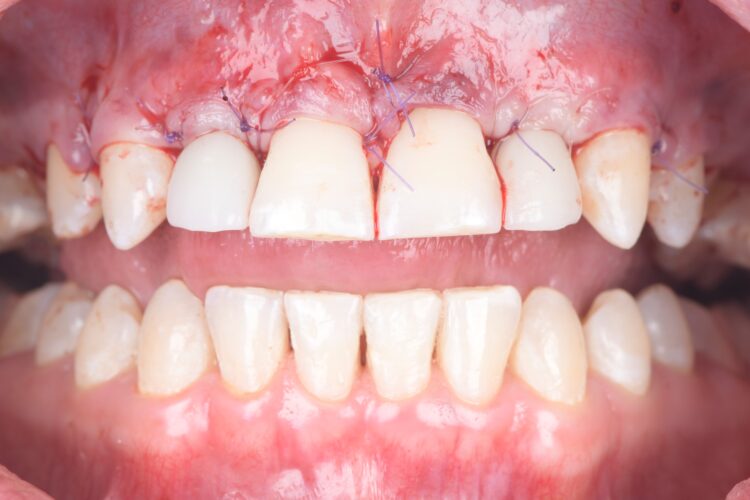

The implant surgery was performed in May 2023 and was filmed live as part of a surgical demonstration for the delegates on a guided surgery course being run by the Fitz Fahey Academy. Implants were placed in the UR2 and UL2 spaces with simultaneous hard and soft tissue grafting. Following the surgery, the patient was provided temporary teeth and instructed to avoid putting undue pressure on the implants during healing.

A week after the surgery, the patient was seen for a healing review, during which X-rays were taken and sutures were removed. After sufficient healing, the patient returned for an impression appointment, where the temporary teeth were removed and scans were taken to fabricate the final crowns.